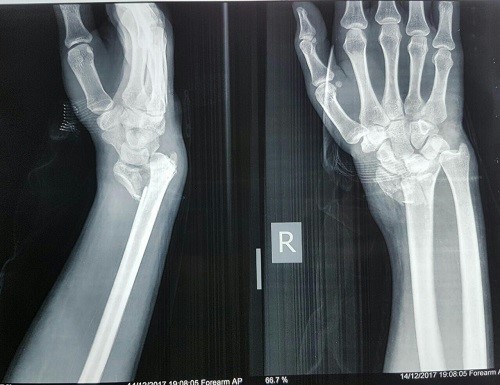

۱. شکستگیهای دست و مچ:

شکستگیهایی مانند شکستگی استخوان اسکافوید (ناوی) در مچ، یا شکستگیهای متاکارپال (مشابه مشت زدن) نیازمند دقت بسیار در توانبخشی هستند. بیحرکتی طولانیمدت پس از گچگیری یا جراحی میتواند منجر به خشکی مفاصل، آتروفی عضلانی و ایجاد چسبندگی در تاندونها شود. هندتراپی با زمانبندی دقیق، مانع از این عوارض و تسهیلکننده جوشخوردگی صحیح است.